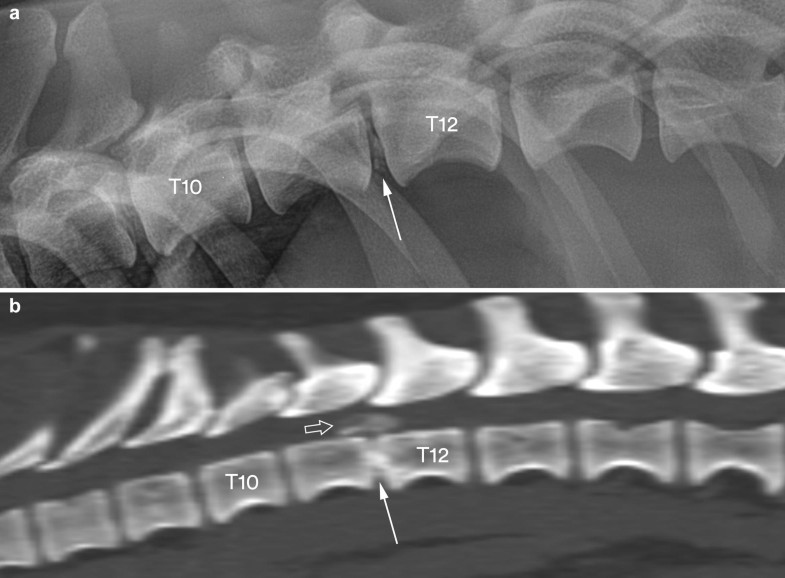

From actavetscand.biomedcentral.com

Calcification of extruded intervertebral discs in dachshunds a What Is A Spinal Lesion In Dogs intervertebral disc disease (ivdd) in dogs is a neurologic condition affecting the spinal cord. acute spinal cord injury is a major cause of neurologic dysfunction in dogs and somewhat less so in cats. in dogs, neoplasms commonly affecting the spinal cord include osteosarcoma, fibrosarcoma, meningioma, nerve sheath tumor, and. the spinal medulla in dogs has a. What Is A Spinal Lesion In Dogs.